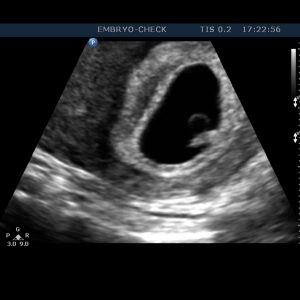

Η EMBRYOCHECK είναι εξειδικευμένη σύγχρονη μονάδα εμβρυομητρικής ιατρικής και εμβρυϊκής καρδιολογίας, αφιερωμένη στην υγεία της γυναίκας – μητέρας και του εμβρύου της και μελλοντικού παιδιού της. Ιδρύθηκε το 2006 και παρέχει υπηρεσίες που καλύπτουν όλο το φάσμα υπερηχογραφικής απεικόνισης στην μαιευτική και γυναικολογία. Βρίσκεται στο κέντρο της Αθήνας έναντι του Μεγάρου Μουσικής.